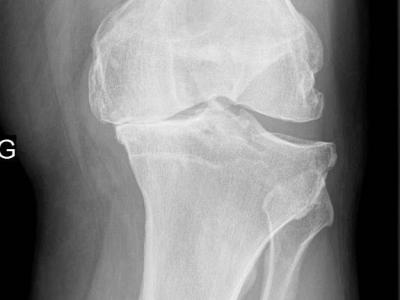

Metformin Effective in Osteoarthritis The diabetes drug metformin provided overweight/obese patients with osteoarthrit

Metformin Effective in Osteoarthritis The diabetes drug metformin provided overweight/obese patients with osteoarthritis (OA) of the knee with significantly greater pain relief than did placebo in a small randomized trial, researchers said. https://t.co/7krvFFfRFC https://t.co/XY5BtiXkOB